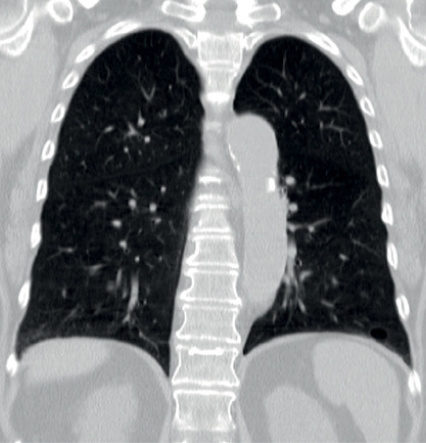

Image

Ansicht des Bauchraums